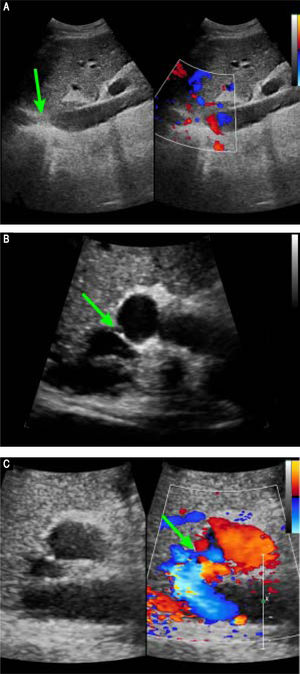

Preoperative contrast-enhanced CT revealed marked atrophy of right lobe of the liver and compensatory enlargement of left lobe, no liver mass, and splenomegaly. Vascular findings were a membranous obstruction of the IVC with dilatation of the upper lumbar tributaries and hemiazygous/azygous veins (Figure 1A); a whole-course obstruction of the right HV; a membranous obstruction of the middle HV and left HV at the orifice of the HV (Figure 1B); and a dilated phrenic vein and pericardial vein, draining blood from the middle HV and the left HV to the superior vena cava. Portal venous-phase images revealed a side-to-side anastomosis of 2 mm diameter between the PV and IVC (Figure 1C). The splenic and superior mesenteric veins were normally oriented and joined to form the main PV. These results were consistent with those of abdominal Doppler ultrasound (Figure 2). The diagnosis of type II Abernethy malformation and BCS was made.

Preoperative Doppler ultrasound images. A. Abdominal two-dimensional ultrasound and three-dimensional Doppler ultrasound images reveal a membranous obstruction of the intrahepatic IVC without blood flow (arrow). B. Abdominal two-dimensional ultrasound and Doppler ultrasound images reveal that the co-orifice of the middle HV and the left HV have a membranous obstruction and no blood flow, C. Abdominal two-dimensiona ultrasound and Doppler ultrasound images reveal an abnormal connection (arrow) between the porta vein and the IVC.